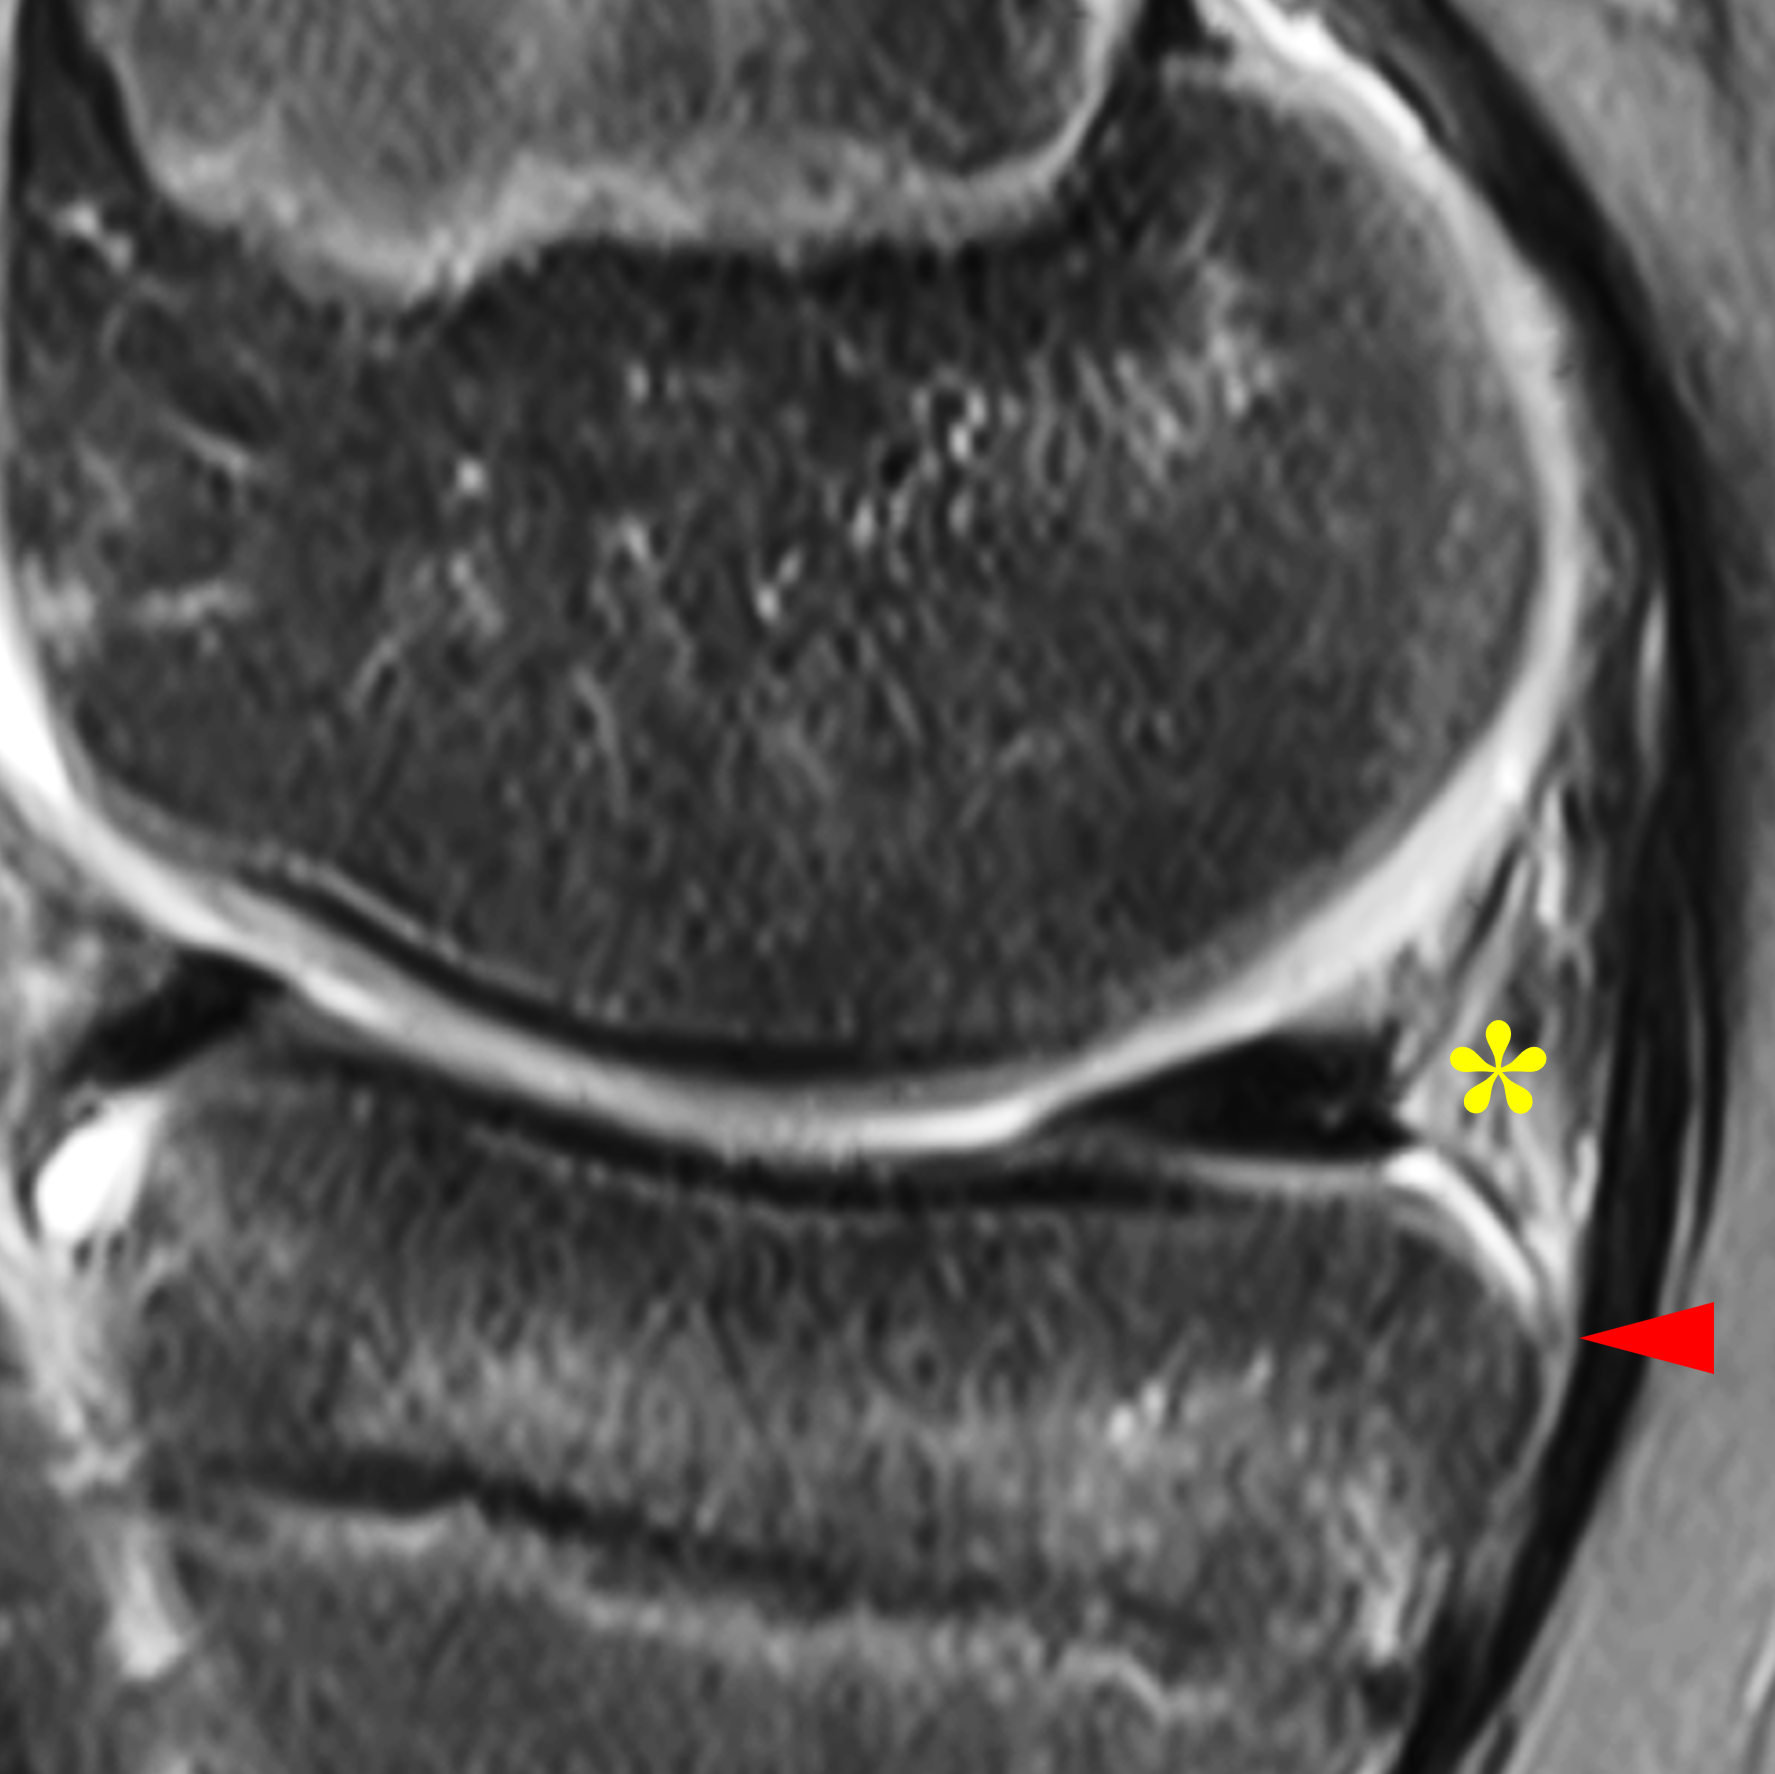

The meniscocapsular and meniscotibial ligaments both arise from the posterior margin of the PHMM (Figures 3 and 4). The meniscocapsular ligament courses posterosuperiorly and blends into the capsule with a variable amount of meniscosynovial tissue covering its superior articular surface. The meniscotibial ligament travels posteroinferiorly and anchors to the posterior tibia several millimeters below the articular surface. The ligaments are comprised of type 1 collagen but are less compacted than typical ligamentous structures, with loose adipose and vascular tissue interposed between the two ligaments.8,21

Figure 4: Normal MRI anatomy of the posteromedial knee. (4A) Sagittal proton density-weighted image shows the meniscocapsular ligament (yellow arrow) and the meniscotibial ligament (red arrow) attached to the posterior horn of the medial meniscus. (4B) Fat-suppressed fluid-sensitive image demonstrates loose connective and adipose tissue (asterisk), which is hyperintense due to its inherent vascularity, between the posterior ligaments. Note the meniscotibial ligament insertion on the tibia several millimeters below the articular cartilage (arrowhead).